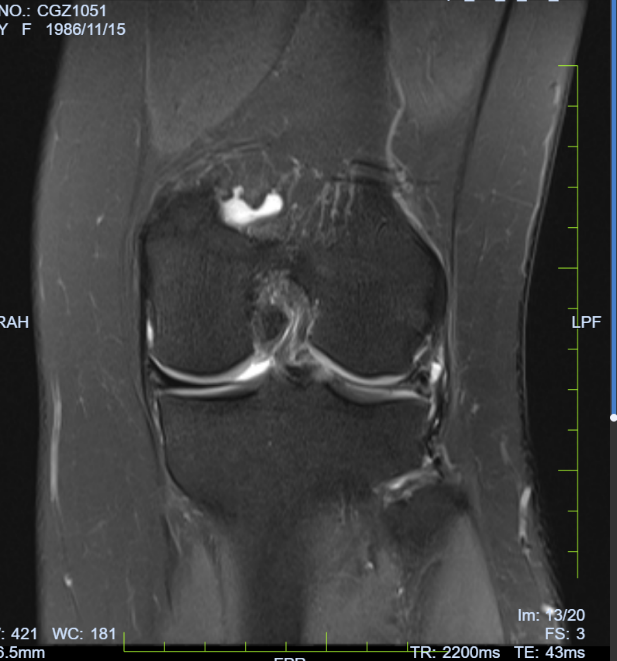

病例七:患者,女,36岁,因“左膝关节疼痛活动受限5天”入院。诊断:左膝外侧半月板撕裂;行左膝关节镜探查+滑膜清理+外侧半月板成形术;手术顺利,术后恢复良好,顺利出院。

左膝外侧半月板撕裂 术前磁共振

左膝外侧半月板撕裂 术中关节手术图片